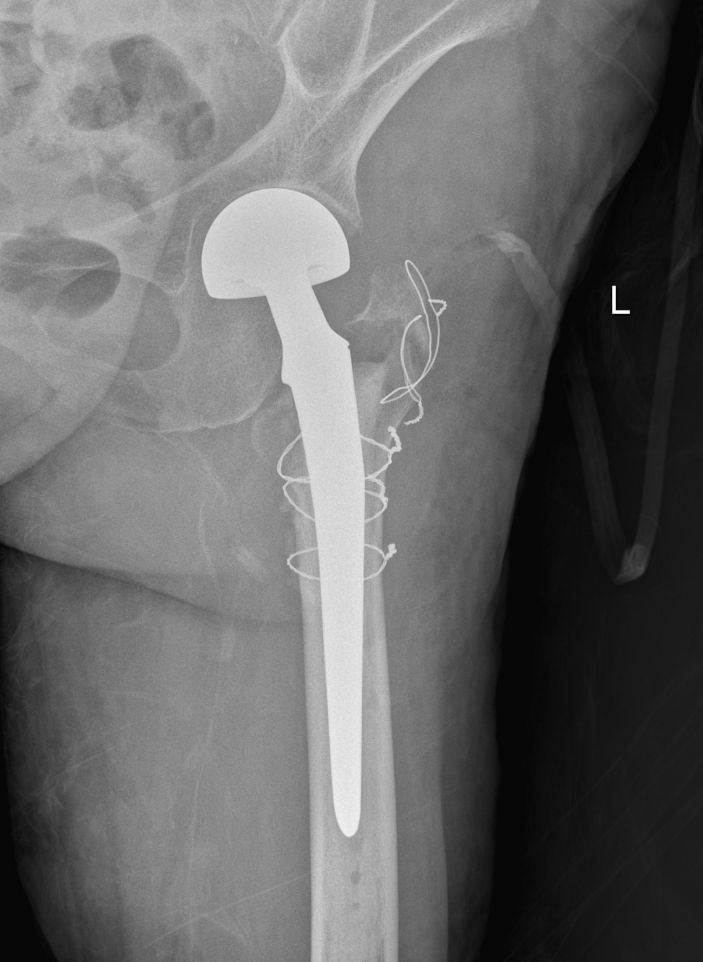

△術後

40月20日,林老太各項生命體征平穩,可耐受手術。在充分的術前準備後,外四科主任吳志斌帶領團隊爲林老太實施手術治療。吳主任充分考慮老人家的骨折特點,采用人工股骨頭置換術,術中給予安裝雙動人工股骨頭,複位髋關節,并仔細把控每一個細節,确保髋部良好的活動性和穩定性,以及雙下肢等長,手術十分成功。